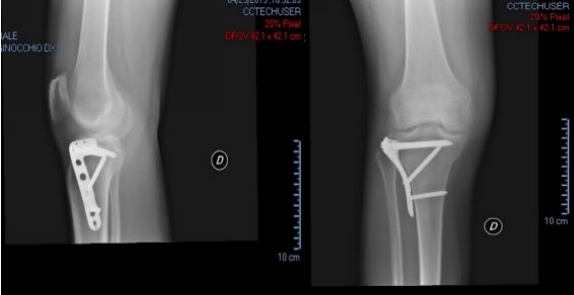

Gli interventi chirurgici più comuni che si eseguono per le affezioni del ginocchio che in generale causano dolore sono:

Oggi, in molti paesi occidentali, è ampiamente riconosciuta la validità della Idrokinesiterapia individuale nella riabilitazione post-chirurgica; consigliamo di iniziarla il prima possibile a seguito dell’approvazione dell'ortopedico, al fine di rispettare i tempi biologici qualora si trattasse di ricostruzioni legamentose, fratture stabilizzate ma non consolidate ecc.

Nella nostra esperienza l'idrokinesiterapia nella ricostruzione del legamento crociato anteriore si può iniziare appena rimossi i punti, mentre per una protesi di ginocchio o in presenza di osteosintesi subito dopo la fase del kinetec.